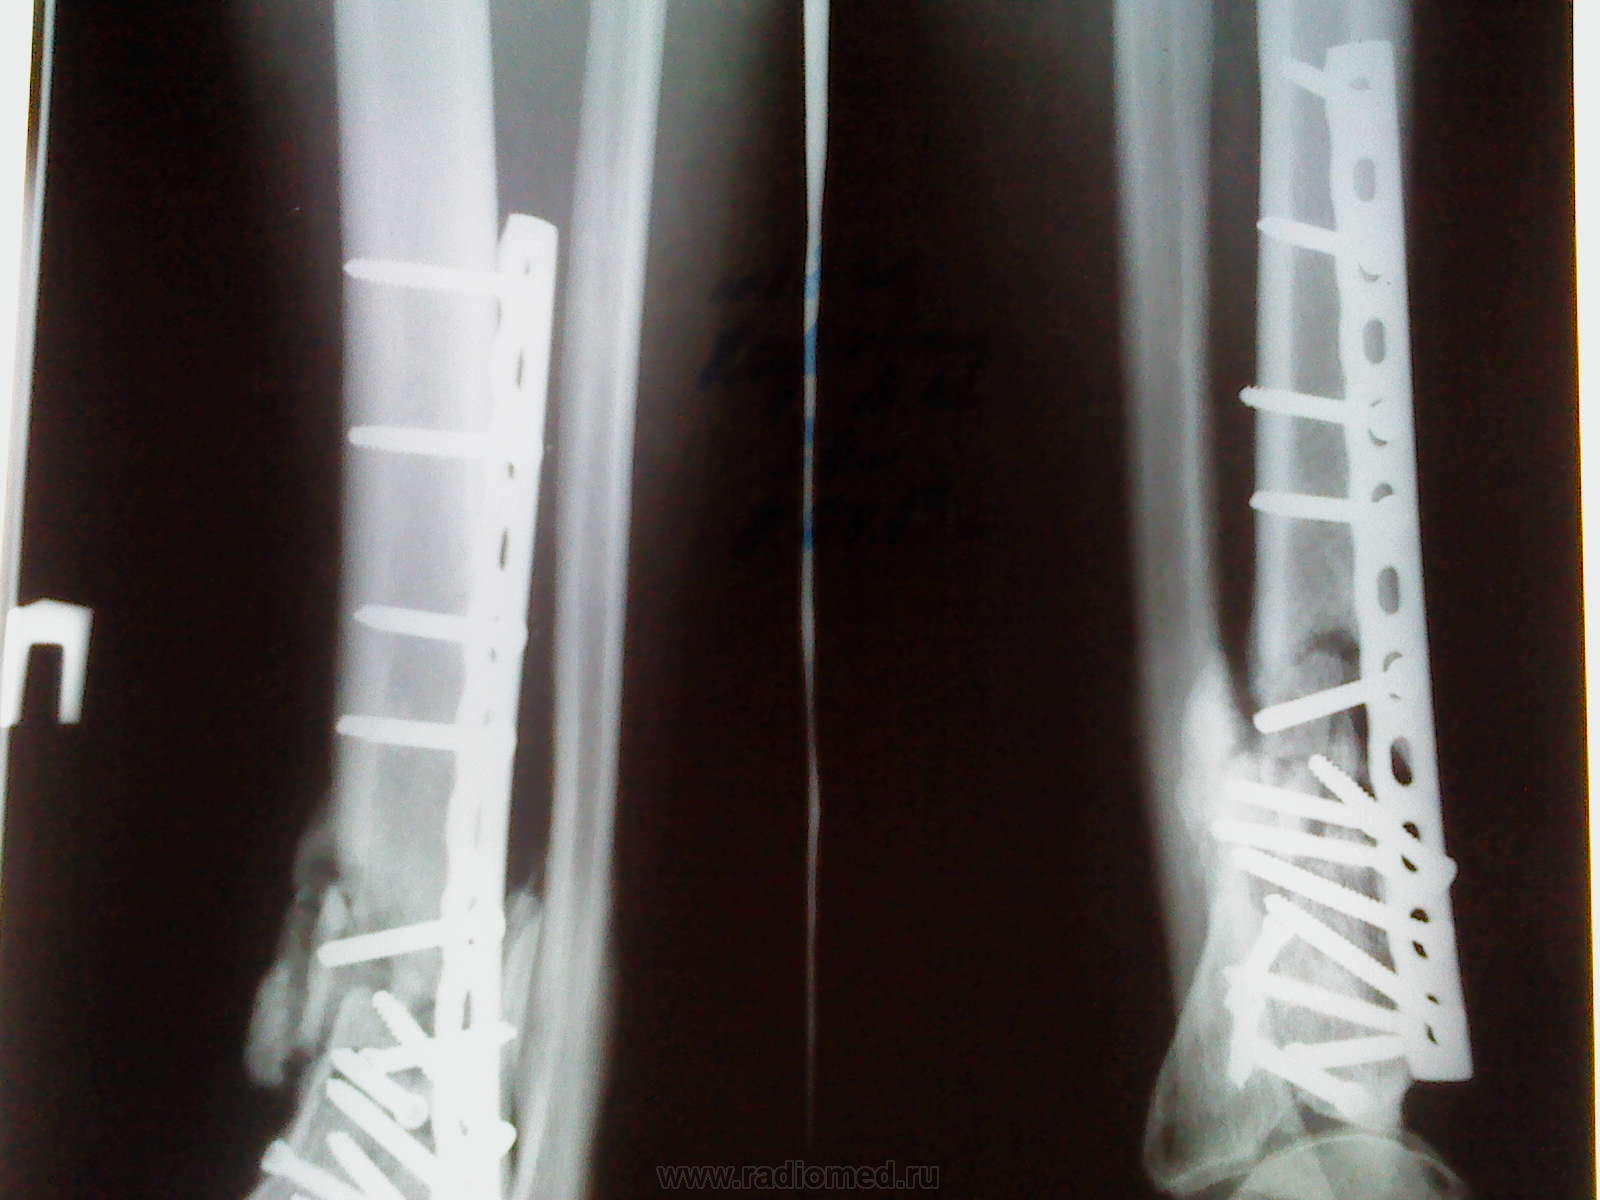

Пациентка, 33 года, Многооскольчатый перелом нижней трети большеберцовой кости. Металлоостеосинтез и репозиция отломков....

Снимок спустя 2 месяца после операции,

Такое чувство , что перед нами коробка с крепёжным инструментом и всё там есть, особенно много шурупов...

Метаэпифиз ББК, наверное, можно было сопоставить и лучше, но не мне судить. Будет артроз и, вполне везможно, анкилоз в г/стопе. Ну а консолидация идет своим ходом, довольно хорошая.

Никто не расссматривает вариант ложного сустава?Очень уж часто встречаются при таких конструкторах. Обычно если есть сомнения делаем КТ!

Лично я рассматриваю вариант трансформации плоского осколка в секвестр и возможного остеомиелита

Андрей Юрьевич! Это один и тот же снимок, только из-за проблем с фотографированием с негатоскопа (фотографировал на дозиметр, да еще и полоски эти...) пришлось его дважды сфотать, немного сместив, чтобы был виден весь конструктор из 15 (!) шурупов с пластиной.

Пы.Сы. А прогноз.... В прогнозе ожидаем остеомиелит большеберцовой кости, и.. надеюсь, все-таки, удаление лишних железок

А могли бы спасти сустав. Теперь все закончится артродезом. Где так ужастно полечили "пилон"